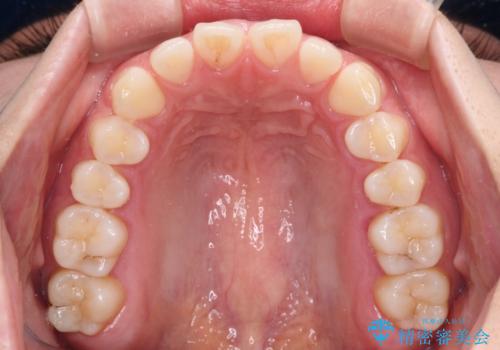

すきっ歯とオープンバイト インビザライン・ライトで改善

- 食いしばりによる顎の負担を気にして来院された患者様です。

当初は、ボツリヌス毒素による咬筋の過緊張の緩和と、睡眠時のマウスピース装着による咬合負担の解消を行いました。

オープンバイトのため、奥歯に負担のかかる咬合状態であったので、矯正治療を提案したところ、希望をされました。

すきっ歯程度の軽度の歯列不正であったため、インビザライン・ライトにより咬合改善を行うこととしました。